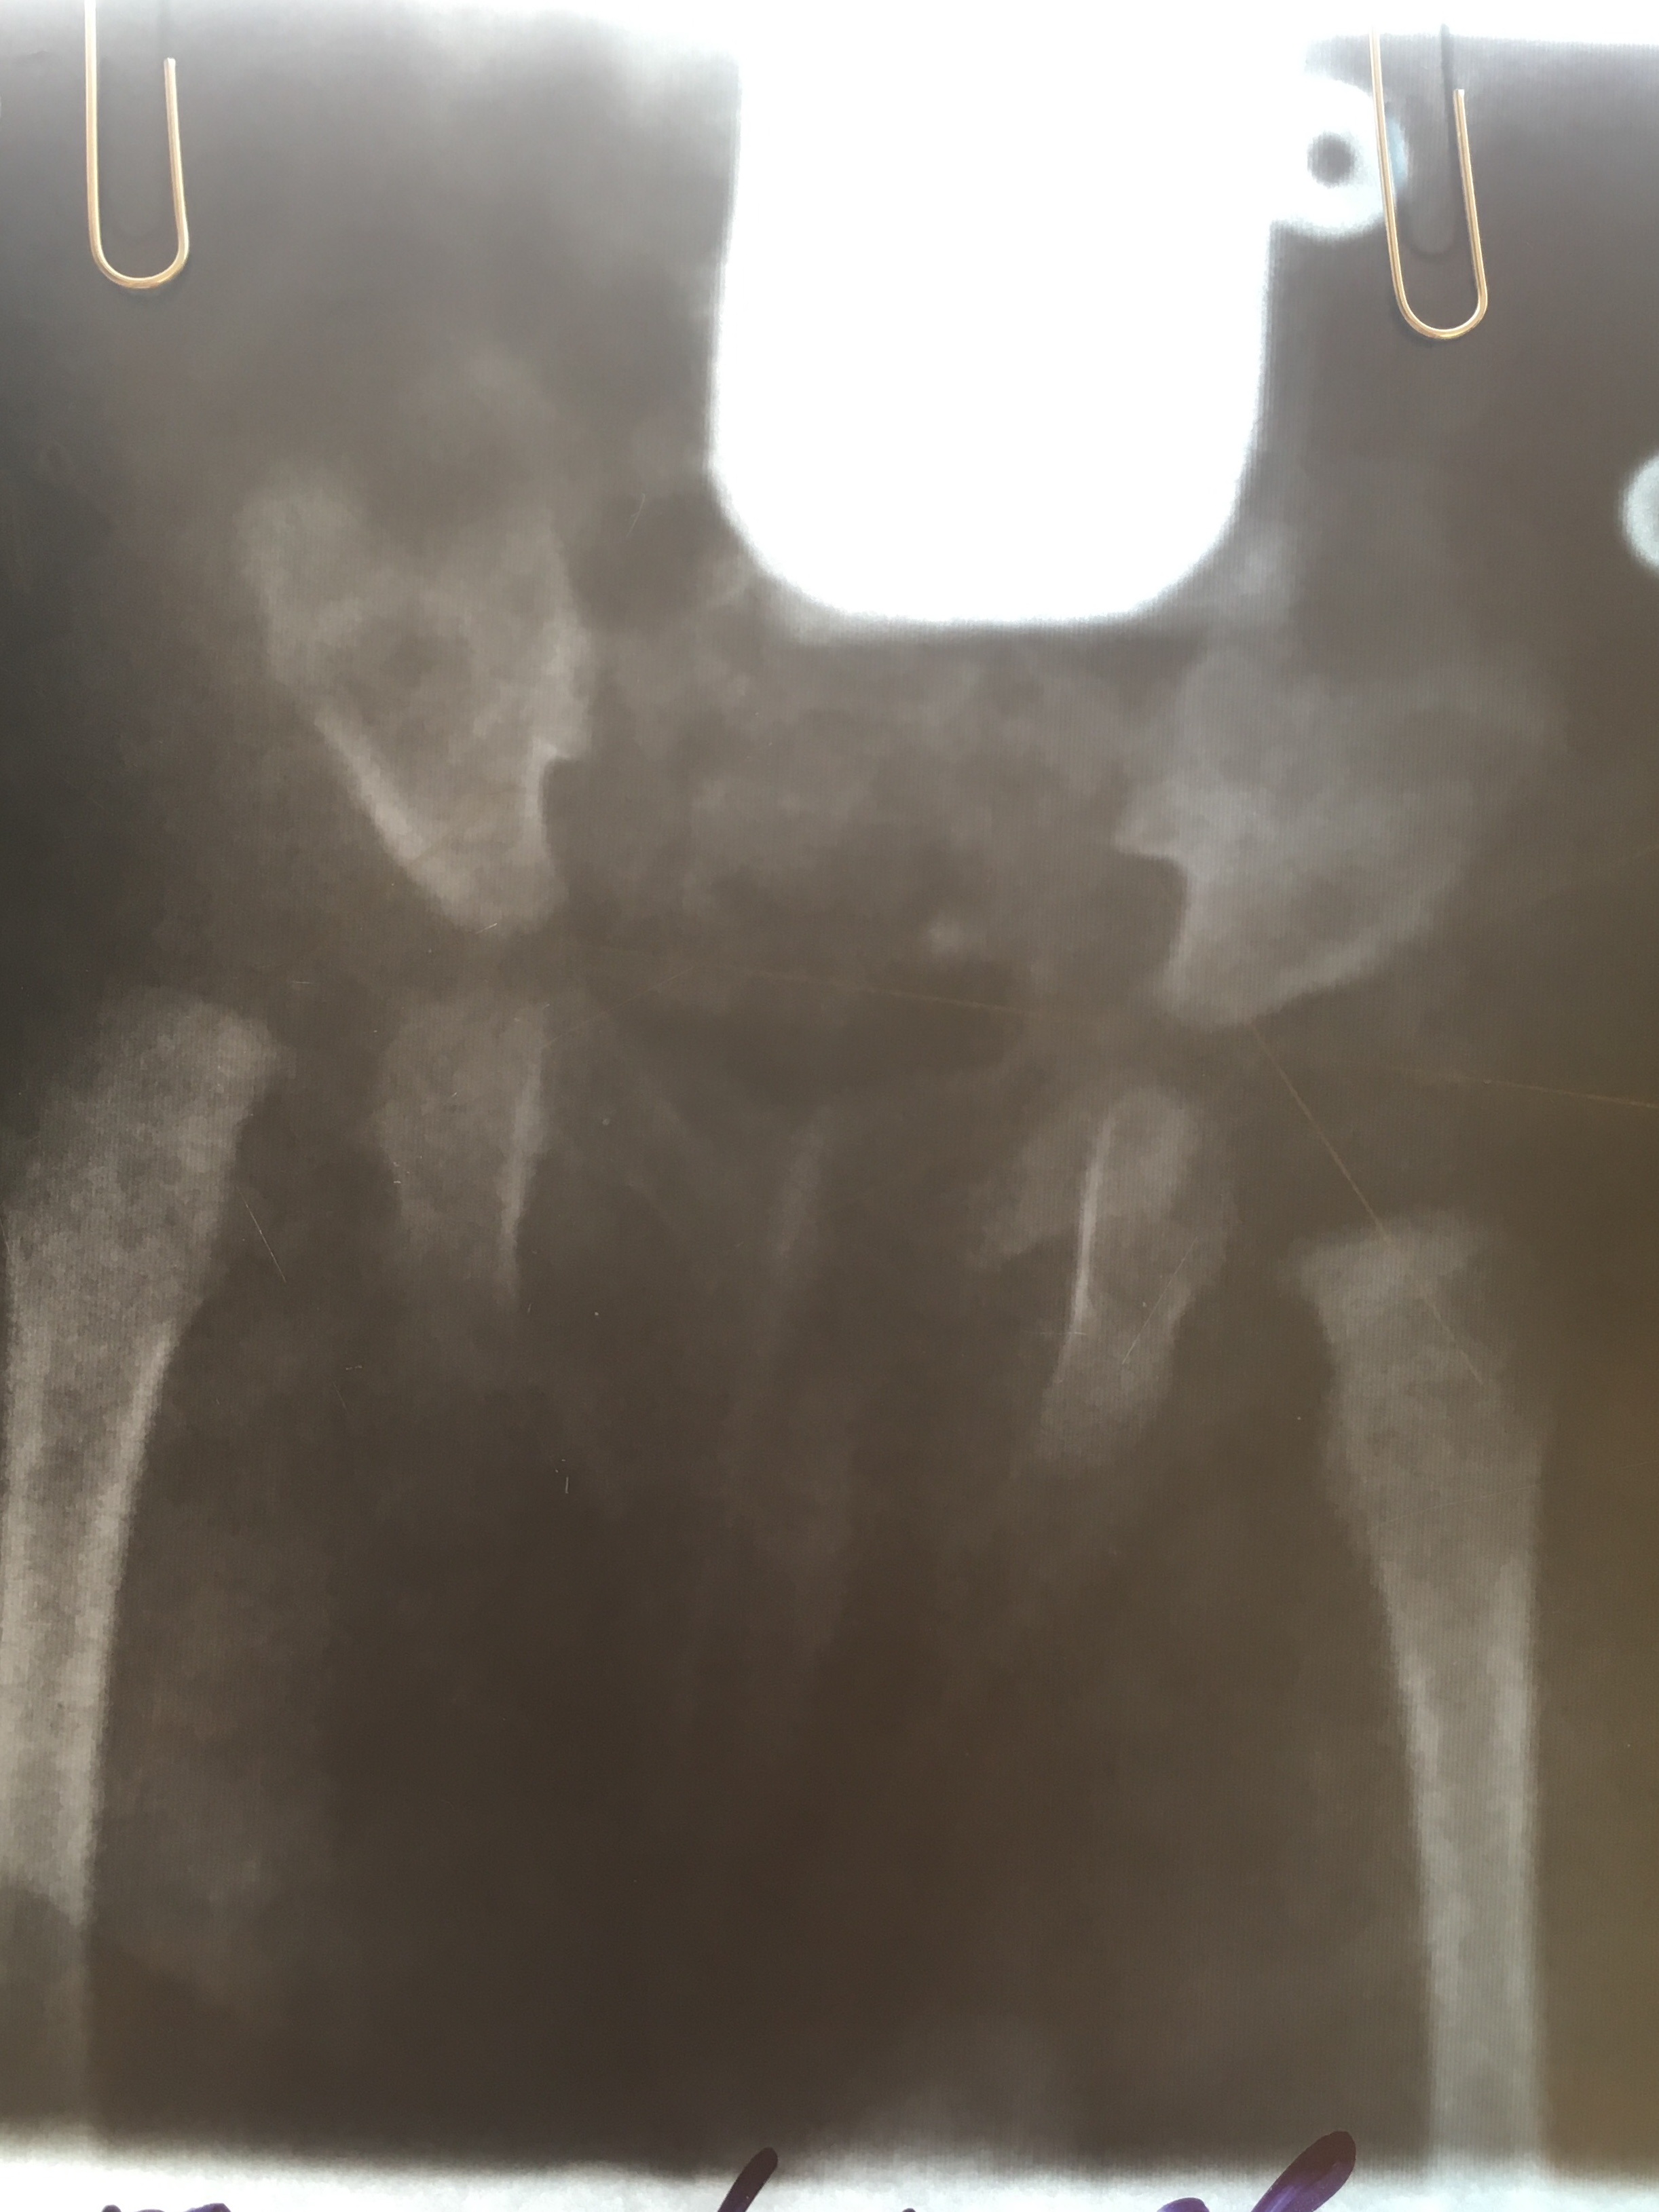

ребенку в 3 мес поставили ДЗ дисплазия справа. Первый снимок ацеб. Индекс справа 40, слева 30. Головка справа децентрирована

2 снимок спустя 3 мес ношения стремян , прохождения процедур . Справа опять 40 гр, слева 25, головки центрированы

спустя месяц: справа 35,продольные оси шеек на медиальный край вертлюжной впадины  .слева 25, на У образный хрящ

опять написано о не симметричной укладке. Скажите правильно ли сделано заключение ? Один ортопед сказал что по таким неровным снимкам судить нельзя . Так ли это? И на последнем снимке опять децентрация ?

Ну, что сказать, у ребенка был врожденный вывих правого бедра. Вы лечитесь, ситуация выправляется. Но считаю, что и справа и слева имеется децентрация шеек бедренных костей, оси направлены на средние трети крыш вертлужных впадин.

Андрей Юрьевич, это по последнему 3 снимку ? А то что снимки не ровные не влияет на углы ? Мне один орторентгенометрия говорил про какие-то параллели , что они не параллельны по снимкам, и поэтому нельзя судить о правильном  измерении. Просто по УЗИ все центрировано ,и скос крыши не такой большой. А тут все не так уж и радужно получается, и на 3 снимке угол 35,нам 8 мес это же тот же почти вывих что и был в 3 мес. Получается ?